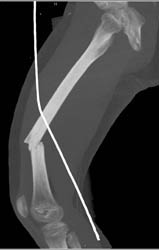

Pins in Acetabulum Near External Iliac Artery